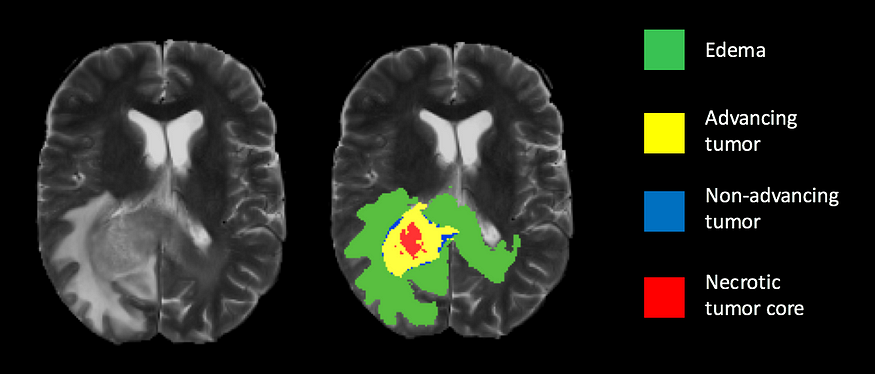

Alzheimer’s disease is a degenerative brain disorder that affects millions of people worldwide. It is a progressive disease that leads to memory loss, cognitive decline, and eventually the inability to carry out basic tasks. Early diagnosis and intervention can improve the quality of life of those affected by the disease. In this tutorial, we will use deep learning techniques to identify Alzheimer’s disease from MRI brain scans.

We will be using the Alzheimer’s Disease Neuroimaging Initiative (ADNI) dataset for this tutorial. The dataset contains MRI brain scans of patients with Alzheimer’s disease and healthy individuals. We will use the T1-weighted MRI images for our analysis.

We can now use our trained model to predict Alzheimer’s disease from MRI brain scans. We will load a sample image and preprocess it before making a prediction.

In this tutorial, we have learned how to use deep learning techniques to identify Alzheimer’s disease from MRI brain scans. We used transfer learning with the MobileNetV2 architecture and achieved good accuracy on the testing data. This technique can be applied to other medical imaging datasets to aid in the early detection and diagnosis of diseases.